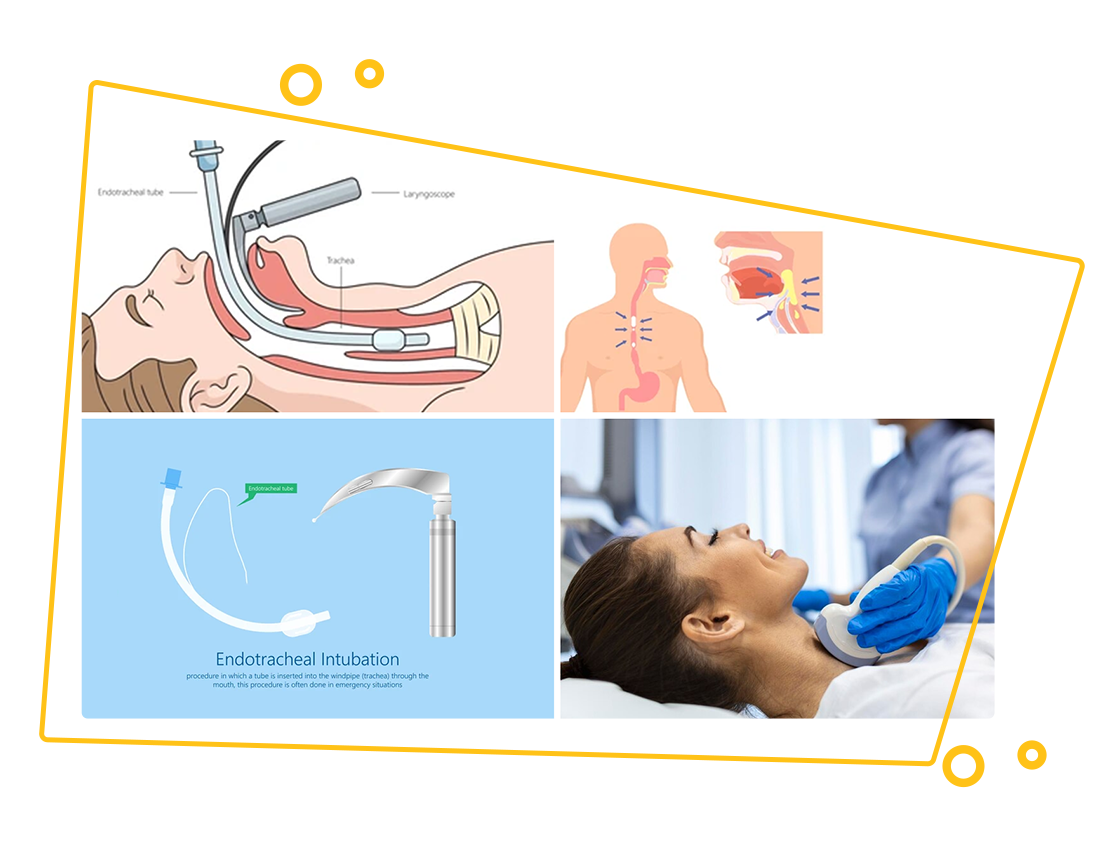

- Laryngoscopy: A procedure where a small camera (laryngoscope) is inserted into the throat to examine the larynx and vocal cords.

- Endoscopy: Involves inserting a thin tube with a camera into the throat to check for abnormalities, often used for investigating persistent symptoms or cancer.

- Stroboscopy: A specialised wave length of light used to evaluate the movement of the vocal cords.

- Micro Laryngoscopy: Surgical technique to remove any lesions or for biopsies of lesions over the vocal cords or the larynx.